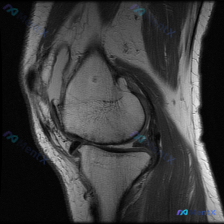

今天整理了一个很有临床意义的读片病例,核心矛盾是「临床怀疑半月板异常,但是单张T1序列MRI没有发现异常」,给大家梳理一下完整的分析思路。

本次提供的是单张膝关节矢状位T1序列MRI影像,核心读片结果如下:

- 骨骼系统:股骨远端、胫骨近端、髌骨骨皮质完整,无骨折、骨质塌陷;骨髓信号正常,无异常低信号病灶

- 关节软骨:股骨髁、胫骨平台软骨厚度和信号均匀,无明显缺损

- 半月板:形态正常呈三角形,内部均匀低信号,未见异常高信号线延伸至关节面,无撕裂征象

- 交叉韧带:前、后交叉韧带走行连续,信号正常,无损伤表现

- 肌腱肌肉:髌腱、股四头肌腱连续性良好,周围肌肉信号正常

- 关节腔与软组织:无明显关节积液,腘窝及皮下软组织无异常肿块

临床提出的核心怀疑是「半月板异常」,基于当前提供的影像,我们先给出直接结论:这张单张T1序列影像上,没有发现半月板撕裂、形态异常或者信号异常,当前影像证据不支持半月板结构性病变。